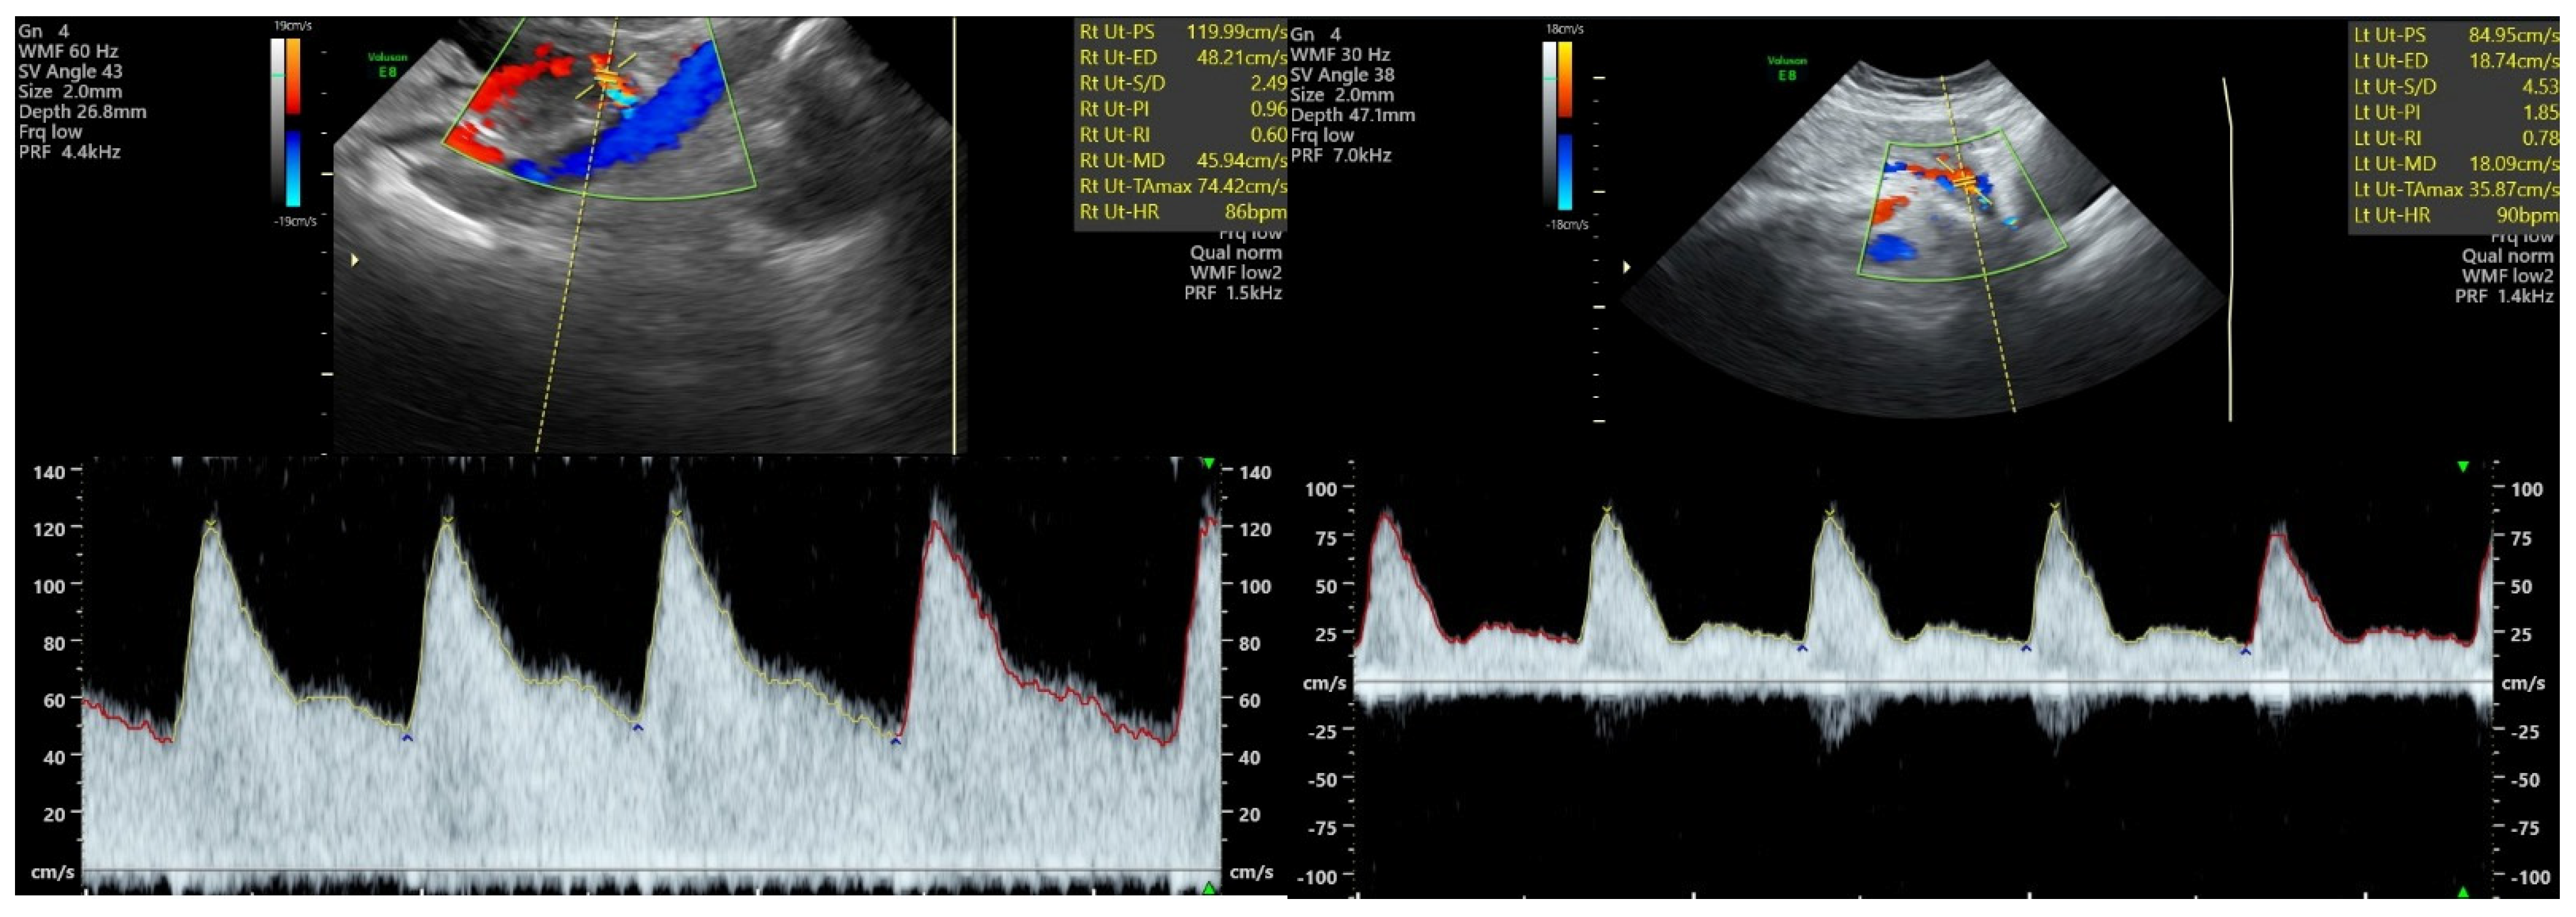

The second trimester transabdominal ultrasound examination technique was performed according to the protocol issued by ISUOG in 2018 [16], consisting of the following steps: firstly, a clear image of the uterus and cervical canal was obtained in a sagittal section; then, the transducer was placed in the right iliac fossae, tilted towards the right lateral wall of the uterus and towards the pelvis. The central or lateral position of the placenta was noticed. Color flow mode was activated and the probe was moved on the right side, maintaining its medial angulation at all times, until the right uterine artery was identified as it crossed the right external iliac artery. We set a narrow Doppler sampling gate of 2 mm and moved it on the right uterine artery at a 1 cm distance from the point of the apparent intersection with the right external iliac artery. While assuring a high-quality view of the right uterine artery with an insonation angle of <50°, the pulsed wave Doppler mode was activated and at least three identical consecutive waveforms of the right uterine artery were obtained. Finally, Doppler parameters PI and RI were measured. The same steps were then used, in order to measure left uterine artery PI and RI, with the probe placed in the left iliac fossae (Figure 1). Mean uterine artery PI and RI were determined as an arithmetic mean of the left and right values in each case. The mean values were used in order to develop the HDP prediction algorithm.

Figure 1. Second trimester Doppler ultrasound scan of the uterine artery at 23−24 weeks of gestation. (Left): normal pregnancy—PI and RI values within normal range. (Right): significantly increased values of PI and RI can be noticed in the case of a pregnancy later diagnosed with early-onset preeclampsia.